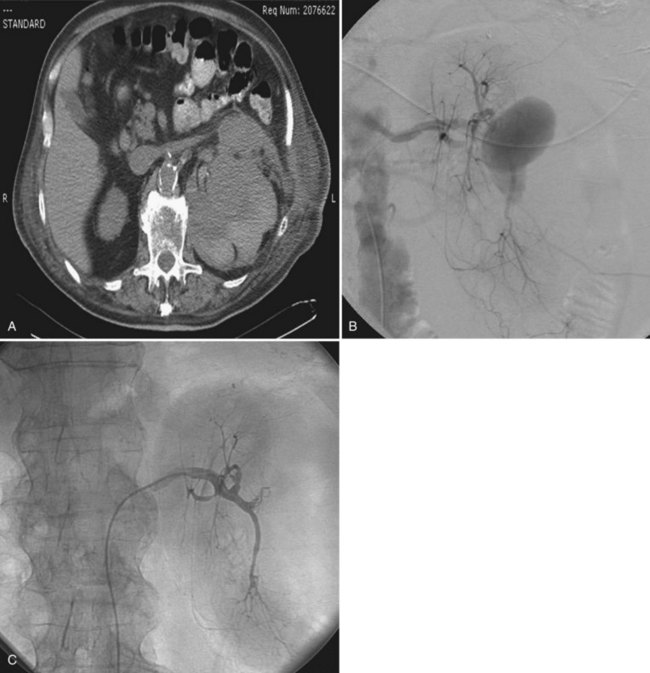

Tumor thrombus involving the IVC should be suspected in patients with lower extremity edema, varicocele, dilated superficial abdominal veins, proteinuria, pulmonary embolism, right atrial mass, or nonfunction of the involved kidney. MR venography is the authors’ preferred study for evaluating the presence and the distal extent of involvement of the IVC (Pritchett et al, 1987; Goldfarb et al, 1990) (Fig. 54–86). The use of invasive inferior vena cavography is limited to those patients with a nondiagnostic MR venogram or ultrasound evaluation, in those in whom MRI is contraindicated, and in patients who underwent preoperative angioinfarction with coils that would produce scatter leading to poor quality MR images (Fig. 54–87). Transesophageal echocardiography (Treiger et al, 1991; Glazer and Novick, 1997) and transabdominal Doppler ultrasonography (McGahan et al, 1993) are also useful. In patients with known IVC tumor thrombus the authors perform intraoperative transesophageal echocardiography to evaluate the distal extent of the tumor thrombus before making the incision.

Figure 54–87 A and B, Preoperative cavogram demonstrating filling defect at the T10 level consistent with tumor thrombus in a patient with a large right renal mass. The patient required cardiopulmonary bypass and deep hypothermic circulatory arrest.

Transesophageal echocardiography is performed before making the incision to evaluate the cephalad extent of tumor thrombus (Fig. 54–102). Radical nephrectomy with removal of a perirenal or infrahepatic IVC thrombus is best approached through a chevron incision. For very large tumors involving the upper pole of the kidney a thoracoabdominal incision may be used instead. Most often these lesions are resected without CPB.

Figure 54–102 A and B, Technique for removing infrahepatic tumor thrombus with assistance of Rummel tourniquets avoiding cardiopulmonary bypass. Ao, aorta; IVC, inferior vena cava; RT. V, right vein.

(© The Lahey Clinic.)